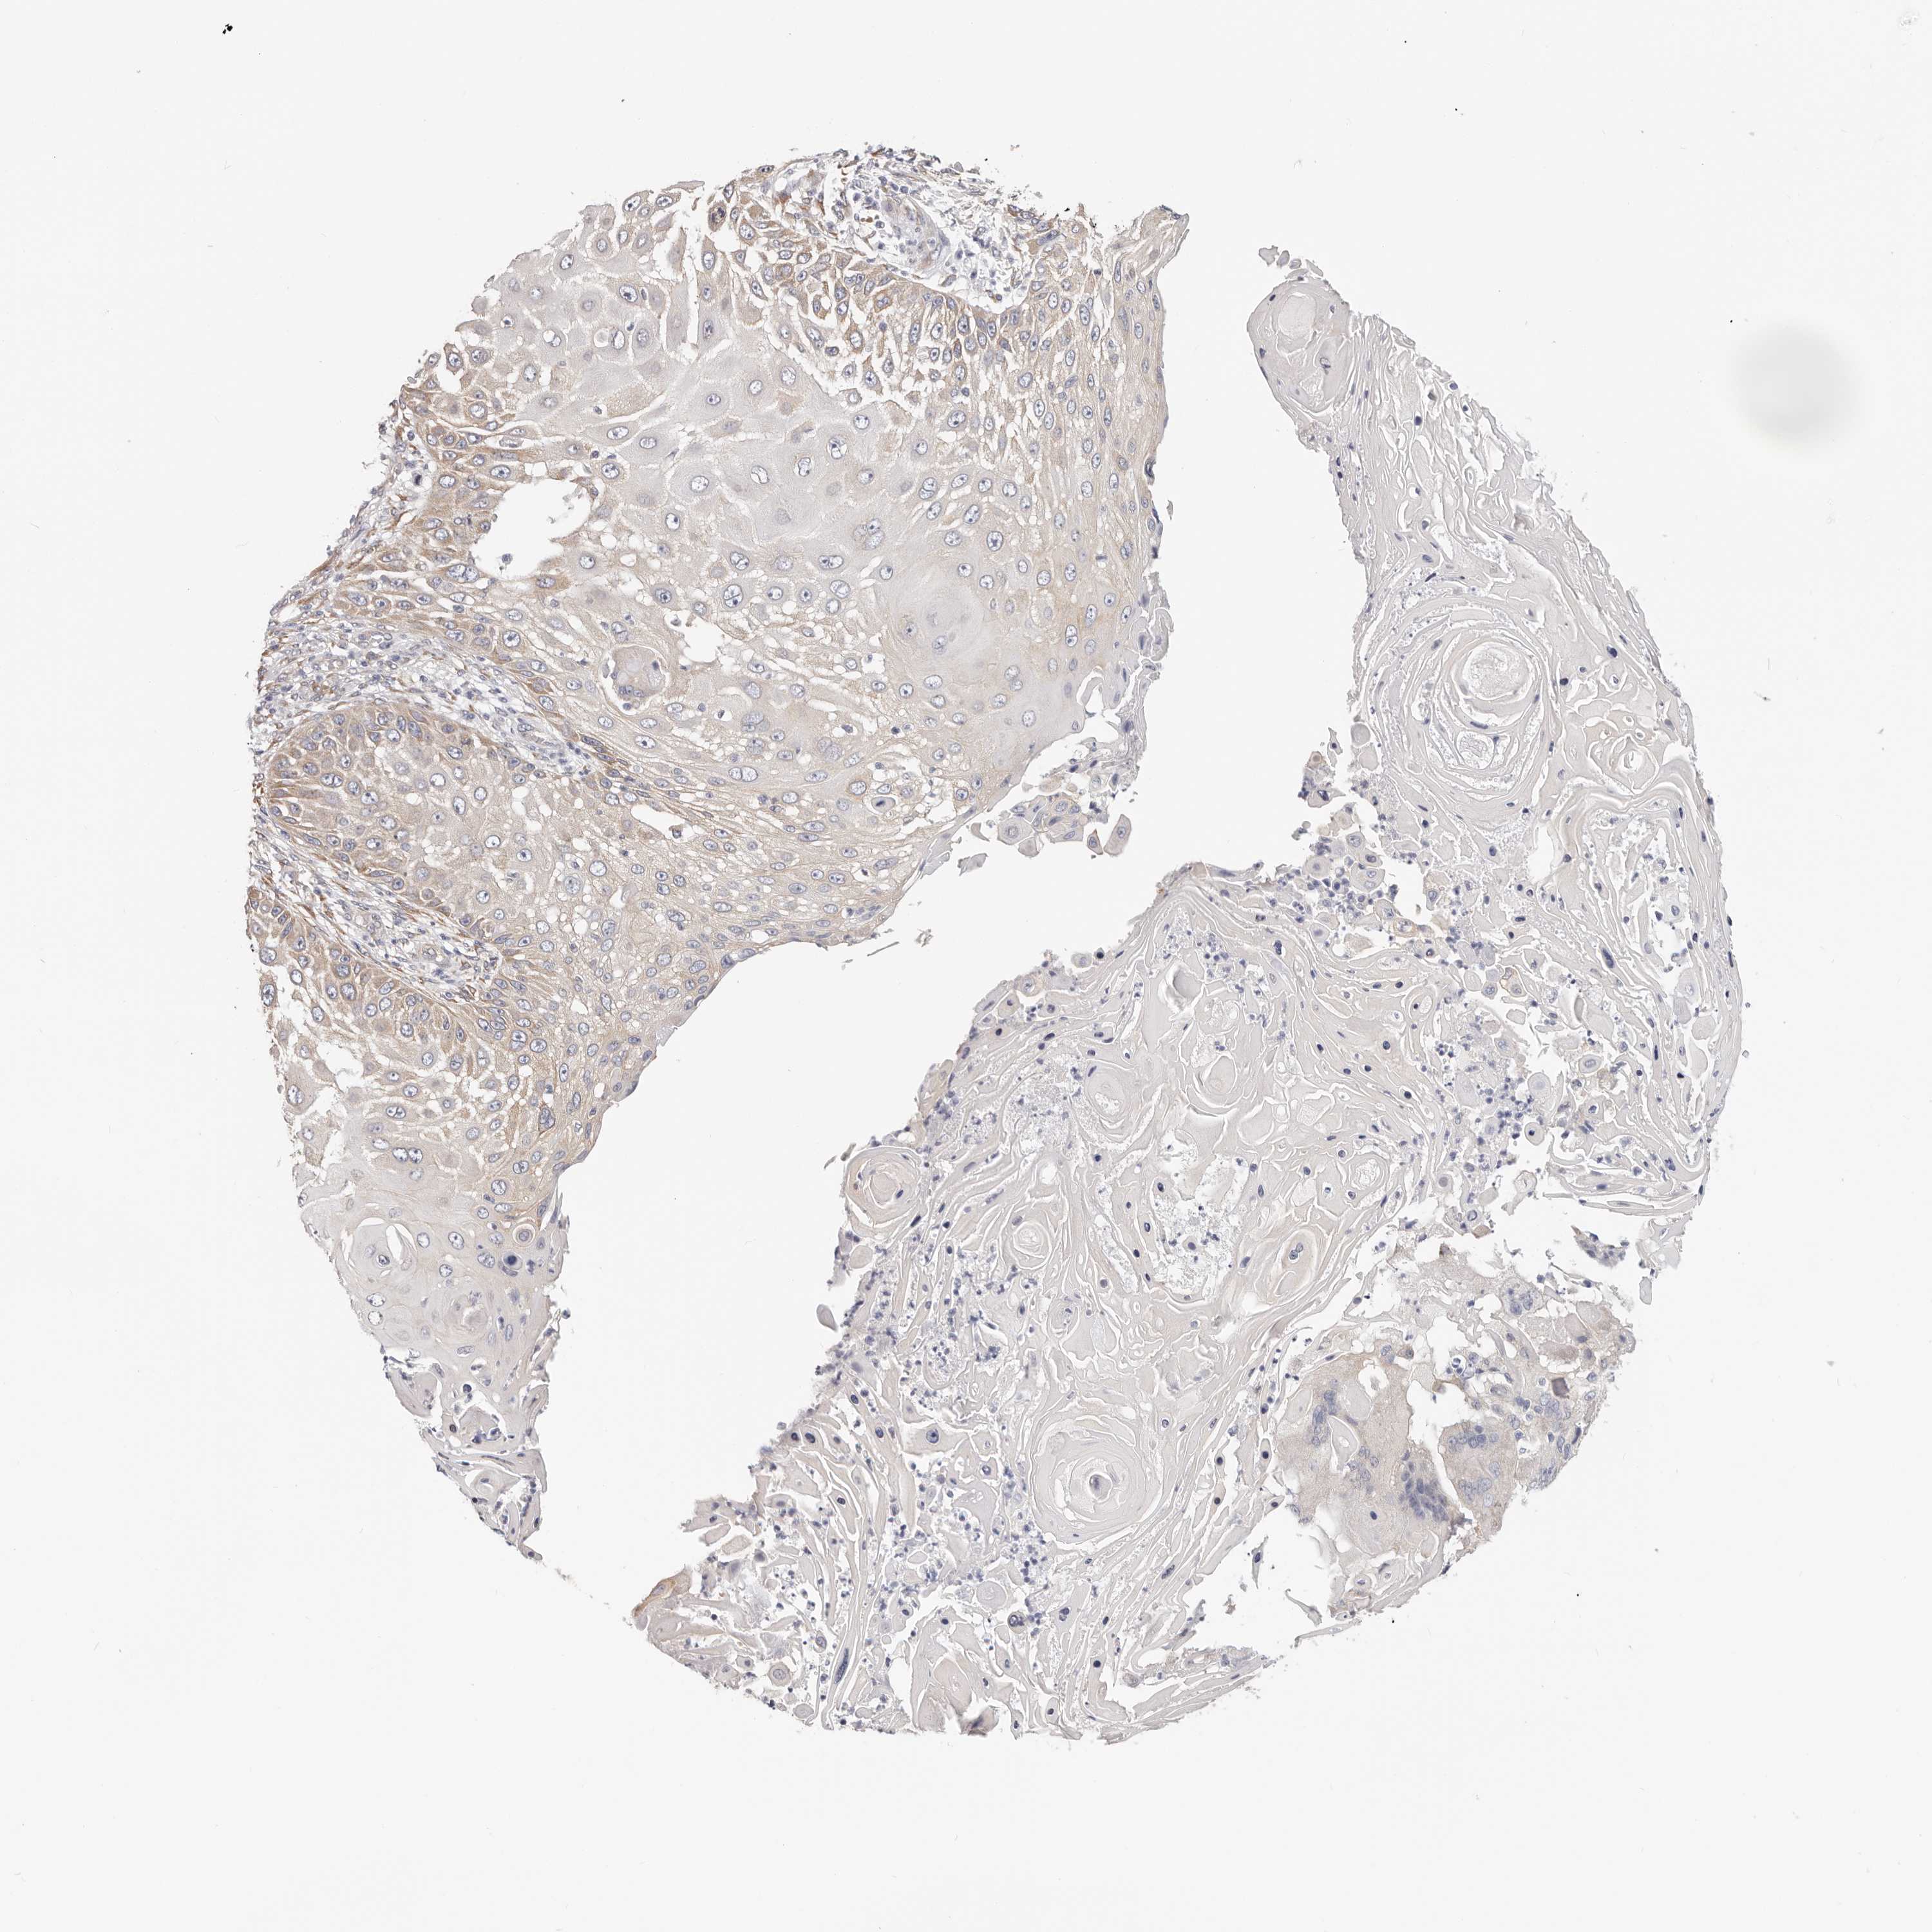

SKIN CANCER - Protein expressioni

A mouse-over function shows sample information and annotation data. Click on an image to view it in a full screen mode. Samples can be filtered based on level of antibody staining by selecting one or several of the following categories: high, medium, low and not detected. The assay and annotation is described here.

Each image is clickable and will lead to virtual microscopy that enables deeper exploration of all samples and also displays staining intensity scores, fraction scores and subcellular localization as well as patient and tissue information for each sample.

HPA030212

HPA030213

HPA030214

HPA030215

CAB013496

Staining

High

Medium

Low

Not detected

Intensity

Strong

Moderate

Weak

Negative

Quantity

>75%

75%-25%

<25%

None

Location

Nuclear

Cytoplasmic/membranous

Cytoplasmic/membranous,nuclear

Basal cell carcinoma

Squamous cell carcinoma, NOS

Squamous cell carcinoma, metastatic, NOS

Adnexal tumor, benign